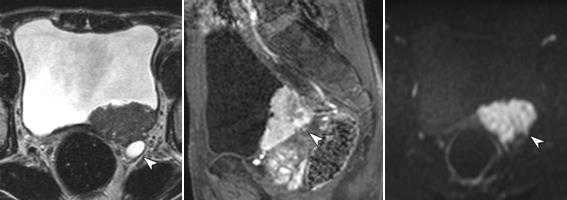

Мужчина, 72 года. В заднее-левых отделах мочевого пузыря визуализирвется объемное образование (уротелиальная карцинома), стадия 3b.

(а) Аксиальное T2-взвешенное изображение показывает больших размеров опухоль с инвазией мышечной стенки и развитием гидроуретера (стрелка). Видна инвазия мышечного слоя, но достовено судисть о паравезикальном распространении невозможно.

(б) Динамическое контрастирование на скане, проходящем перпендикулярно к основанию опухоли выявляет тотальное поражение стенки пузыря, нечеткость заднего контура опухоли.

(в) Поперечное диффузионно-взвешенное изображение демонстрирует большую опухоль с признаками трансмурального роста и инвазии в паравезикальную клетчатку (стрелка).